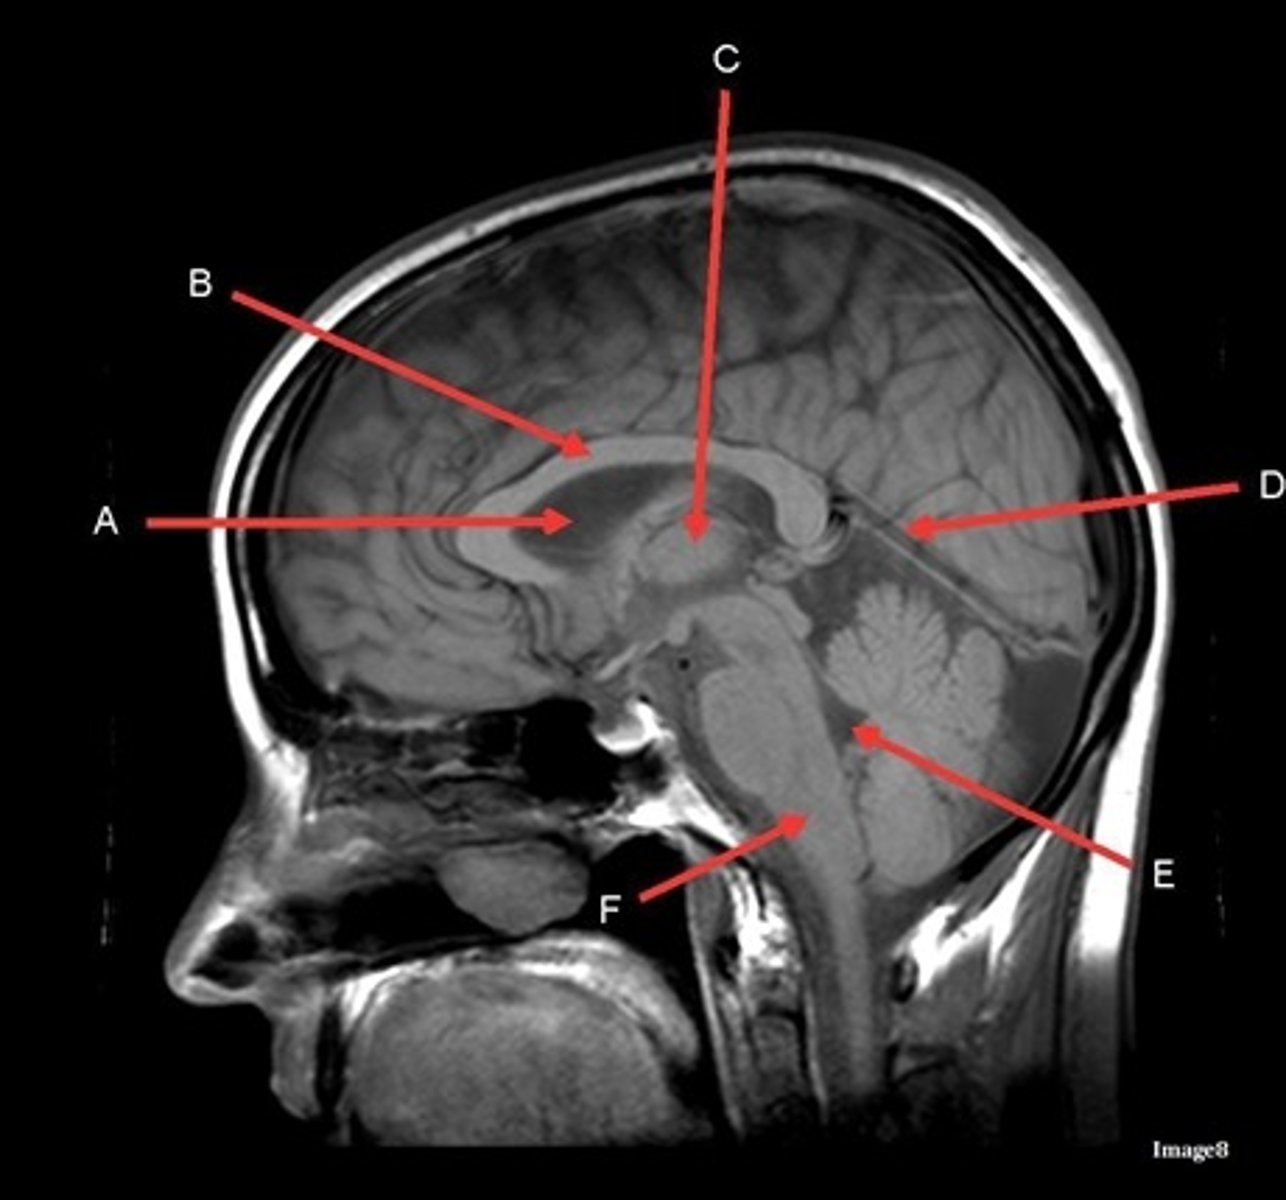

T1, sagittal

A- region

Genu of Corpus Callosum

B- region

Splenium of Corpus Callosum

A

lateral ventricle

B

corpus callosum

C

thalamus

D- separates what

tentorium cerebelli- cerebrum (occipital and temporal lobes) from brainstem and cerebellum

E

fourth ventricle

F

medulla oblongata